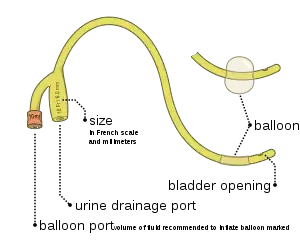

Foley and similar brand catheters usually have two separated channels, or lumina (or lumen), running down its length. One lumen, opens at both ends, drains urine into a collection bag. The other has a valve on the outside end and connects to a balloon at the inside tip. The balloon is inflated with sterile water or saline it lies inside the bladder to stop it from slipping out. Manufacturers usually produce Foley catheters using silicone or coated natural latex. Coatings include polytetrafluoroethylene, hydrogel, or a silicone elastomer – the different properties of these surface coatings determine whether the catheter is suitable for 28-day or 3-month indwelling duration. There is a 3rd type of UC not mentioned above, that has 3 lumens for using for bladder washouts post prostate surgery, 1 lumen is for urine flow out, 1 lumen is for saline flow in (bladder washouts solution), and the 3rd is for the balloon to be inflated.

Sizes

The relative size of an indwelling urinary catheter is described using French units (Fr).[5] Alternatively, the size of a 10 Fr catheter might be expressed as 10 Ch (Charriere units – named after a 19th century French scientific instrument maker, Joseph-Frédéric-Benoît Charrière). The most common sizes are 10 Fr to 28 Fr. 1 Fr is equivalent to 0.33 mm = .013" = 1/77" of diameter. Foley catheters are usually color coded by size with a solid color band at the external end of the balloon inflation tube, allowing for easy identification of the size.[6] Note: Colors for French sizes 5, 6, 8, 10 may vary significantly if intended for pediatric patients. Color for French size 26 may also be pink instead of black.